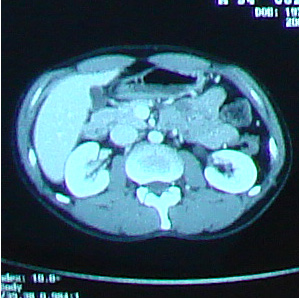

でも、髪質は脱毛前とは全く異なり、硬く、クセの強い、ゴワゴワしたものだった。 いろいろな人の体験記を読んでいたので、そうなるかもしれないこともわかっていたし、実際に抗癌剤治療をしたのだから「ま、そうだろうな」と思っていた。 でも、ここ最近ちょっと様子が変わったらしい。 今日、再び美容室に行った。 美容師さん:「少し柔らかくなったような・・以前はもっとこう・・何と言うか・・」 自分:「硬くてゴワゴワしてましたよね。」 少し髪質が柔らかくなってきたみたい。 いや、治療前の髪質に戻り始めたかな。 髪で風を感じるようになってきたのがちょっぴりうれしい最近です。 先日撮影したCT、採血結果を聞いてきました。 【画像】:変化なし 【HCGΒ】:0.1> 普通に仕事をして、普通に疲れてますが、検査的には問題なし。 この病気、わりと仕事現役世代が多いと思うのですが、みなさん治療後はバリバリ働いているのだろうか。 それで大丈夫なのだろうか。 それにしてもCT画像を見るのはおもしろい。 生きたまま自分の内部が見れるんだから。 毎回診察時に「写真撮っていいですか?」が恒例になってきてる。 先生も「あぁ、どうぞ(苦笑)。あ、撮るならこっちかな。」とか言って該当するほうのフィルムを移動してくれる(笑)。 そうだ、この日は入院時にお世話になった看護士の○澤さんが外来で助手をしてた。 ほとんど話ができなかったけど、この場をかりて 「大変お世話になりました。本当に感謝してます。」